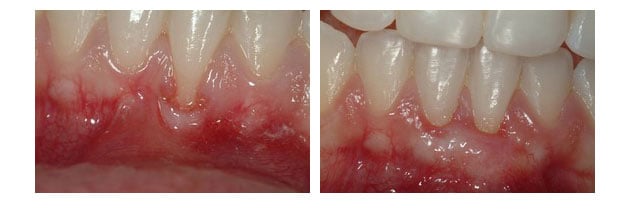

Gum Recession & Gingival Grafting

Gum Recession & Gingival Grafting